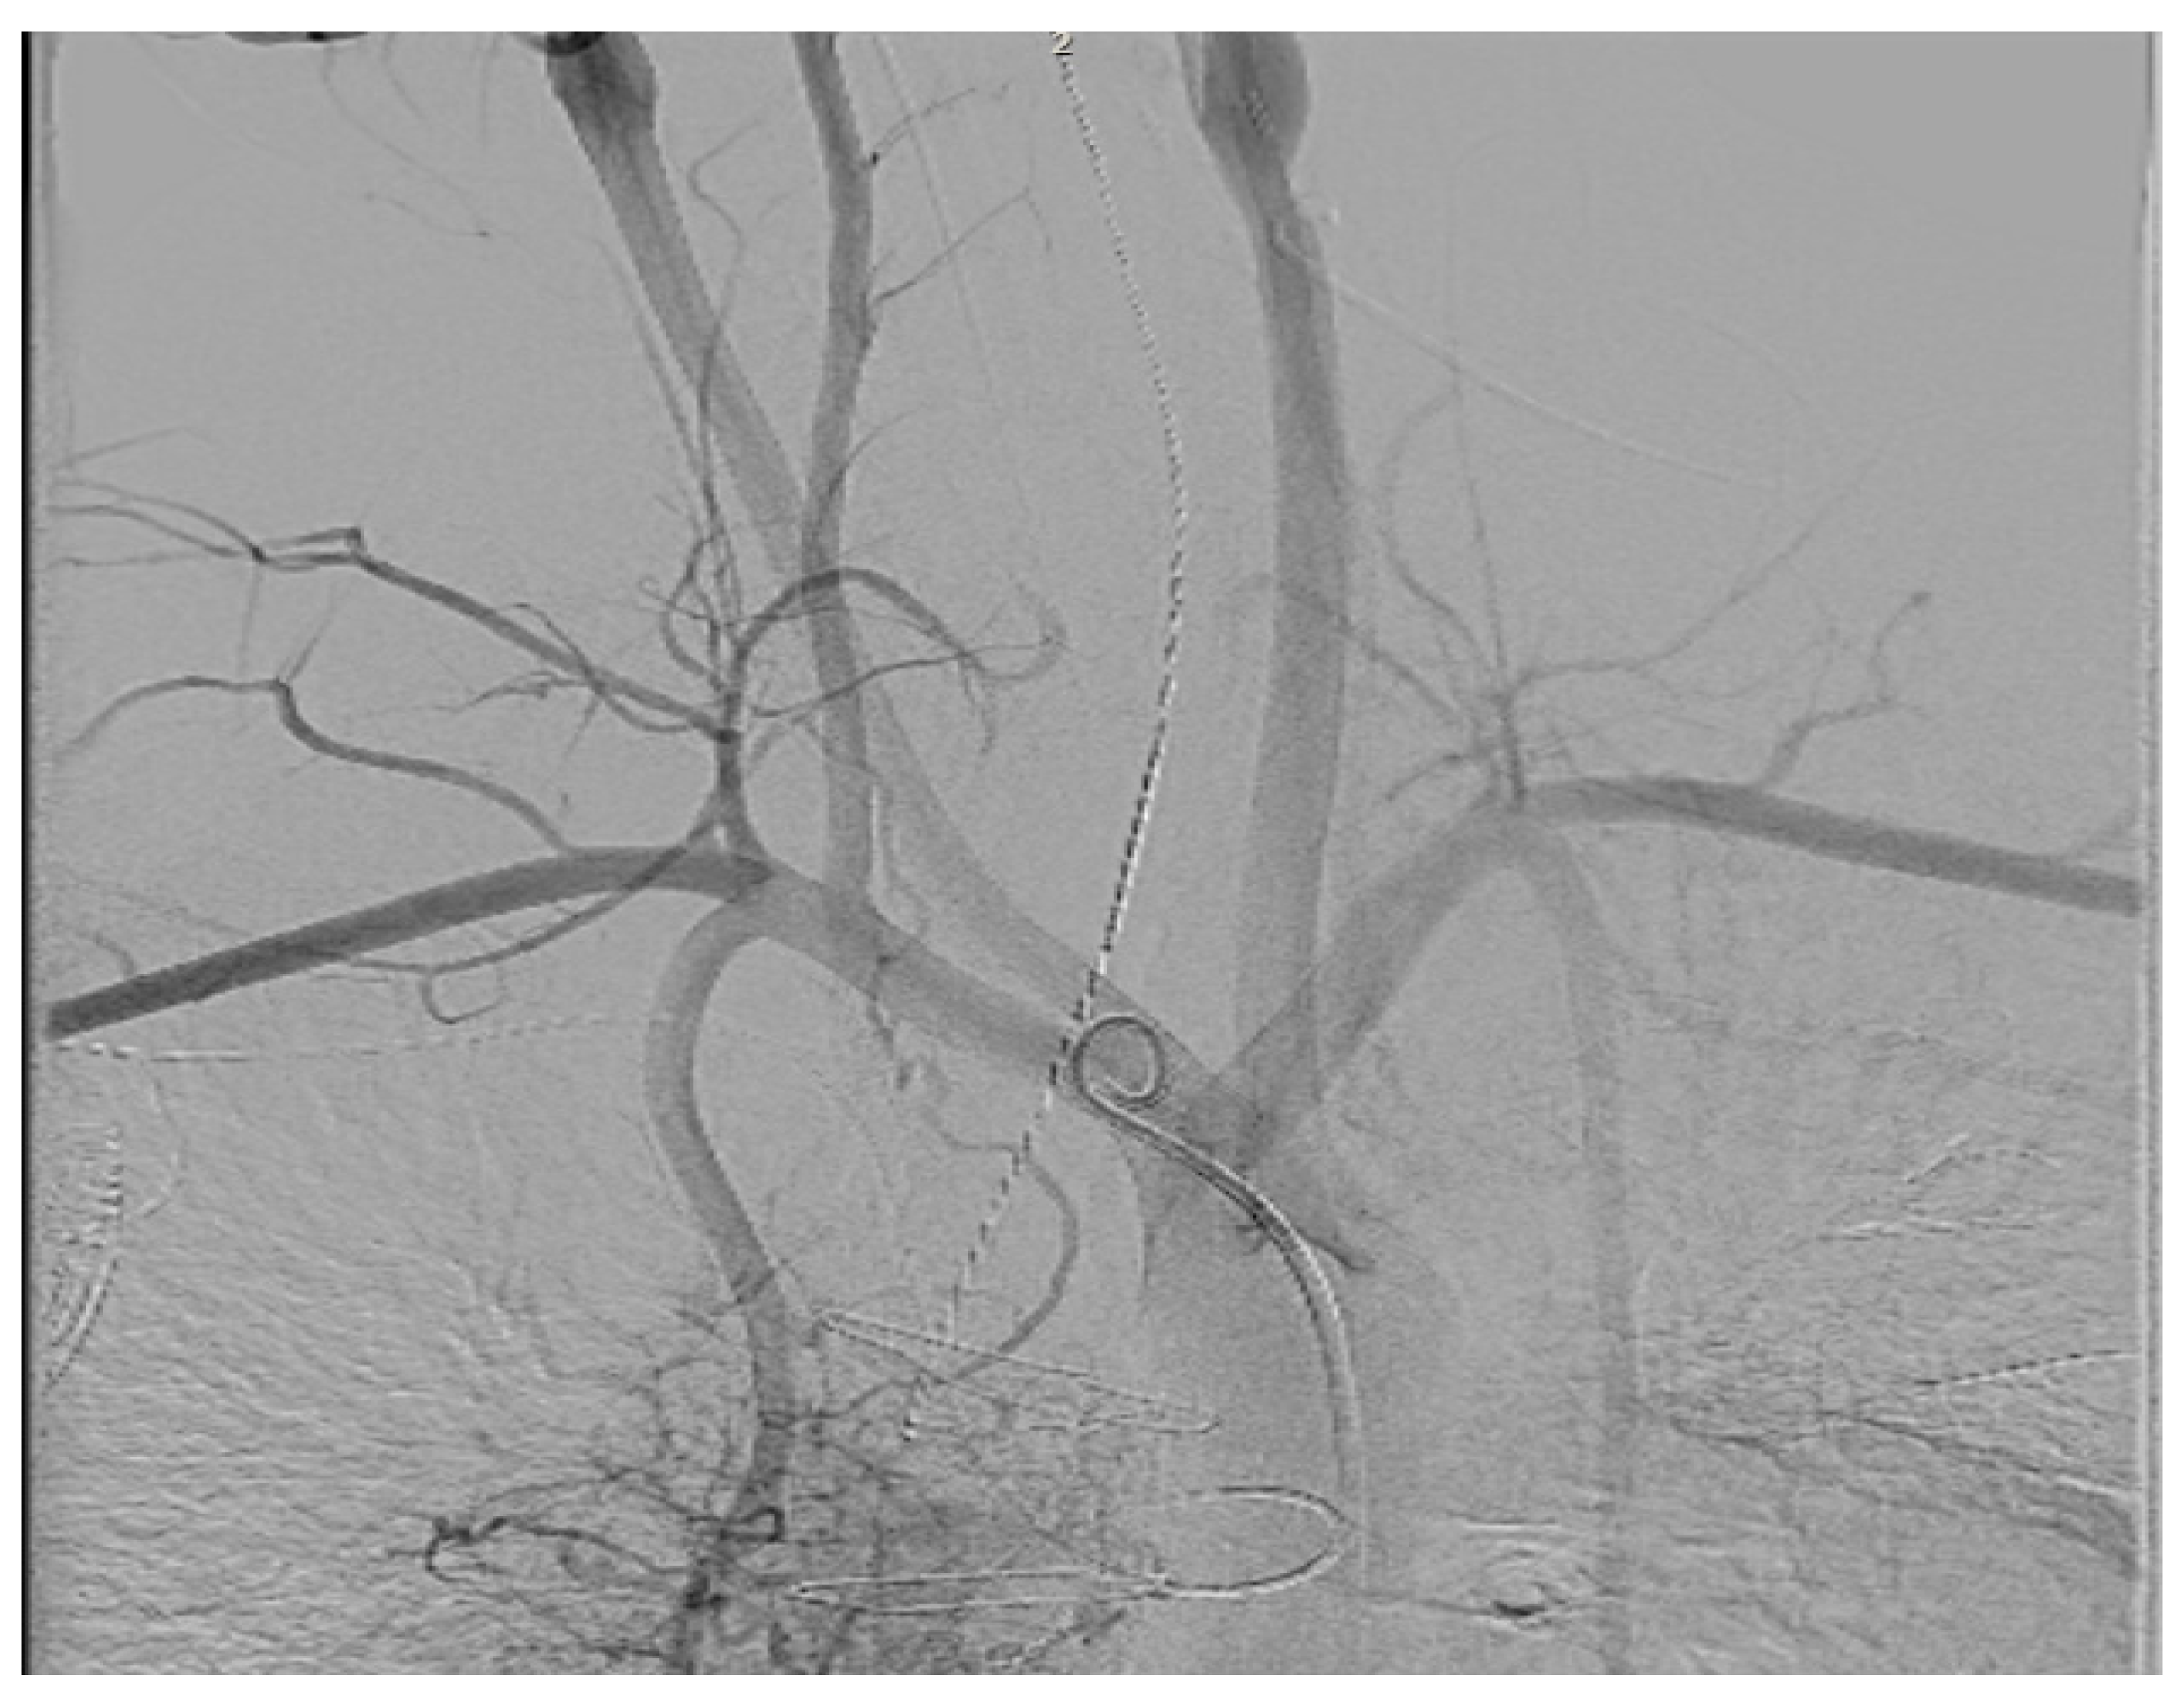

- Goulden, C.J.; Khanra, D.; Llewellyn, J.; Rao, A.; Evans, A.; Ashrafi, R. Novel approaches for leadless pacemaker implantation in the extra-cardiac Fontan cohort: Options to avoid leaded systems or epicardial pacing. J. Cardiovasc. Electrophysiol. 2023, 34, 2386–2392. [Google Scholar] [CrossRef]